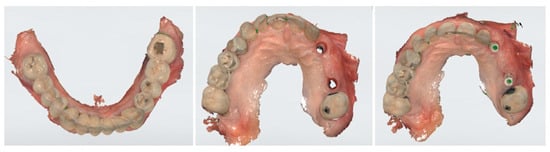

After another 3 months, following the verification of osseointegration, optical impressions were taken for the completion of the final prosthesis (Figure 4). After normal prosthetic phases, a screw retaining a three-unit bridge made of monolithic zirconia was applied (Figure 5). The occlusion and soft tissue compression were verified. After delivery, the occlusal function and soft tissue stability were monitored in the following months.

Figure 4. Optical impressions for completion of the final prosthesis.